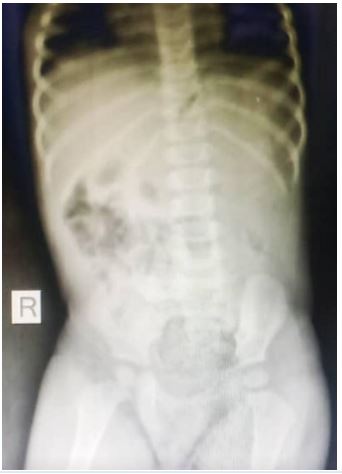

She presented with a plain abdominal radiograph which showed a FB (nail) in the body of the stomach (Figure 1) This was done about 6 hours prior to the presentation at our facility. A repeat radiograph done at the presentation showed the FB (nail) at the region of the terminal ileum (Figure 2). She was commenced on nil per oral, intravenous fluids and monitoring (clinical and radiological). She had two additional plain abdominal radiographs, (Figure 3, 24 hours on admission) and (Figure 4, on day 3). The vital signs remained stable and the abdominal examinations remained equivocal throughout the period of admission. She was discharged following a repeat radiograph which showed no evidence of FB in the GIT.

Figure 4: AP view of plain abdominal radiograph (Day 3).